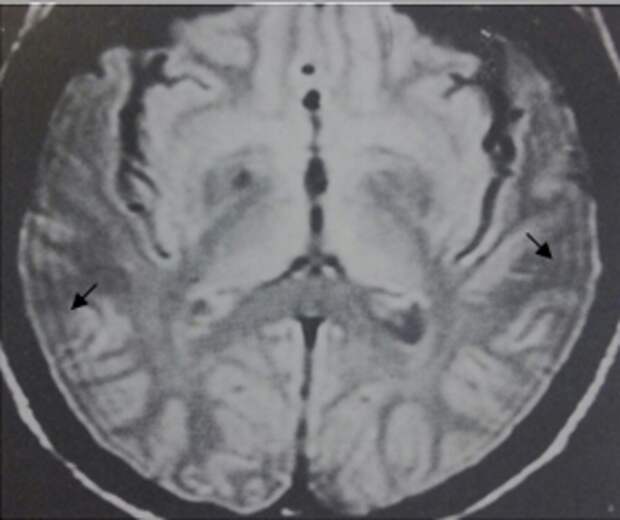

На изображении артефакт проявляется в виде темного ободка с одной стороны и светлого ободка с противоположной стороны от структур, содержащих и воду, и жир, на границе их раздела.

Классические локализации:

- Граница почки и паранефральной жировой клетчатки.

- Контур мочевого пузыря и окружающего жира.

- Граница мышц и подкожной жировой клетчатки.

- Печень и внутрипеченочные жировые включения.